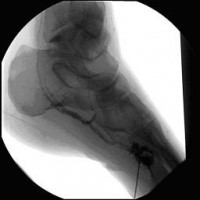

Vor perkutaner transluminaler Angioplastie (PTA) der Unterschenkelgefäße

(Bild 3 von 4)